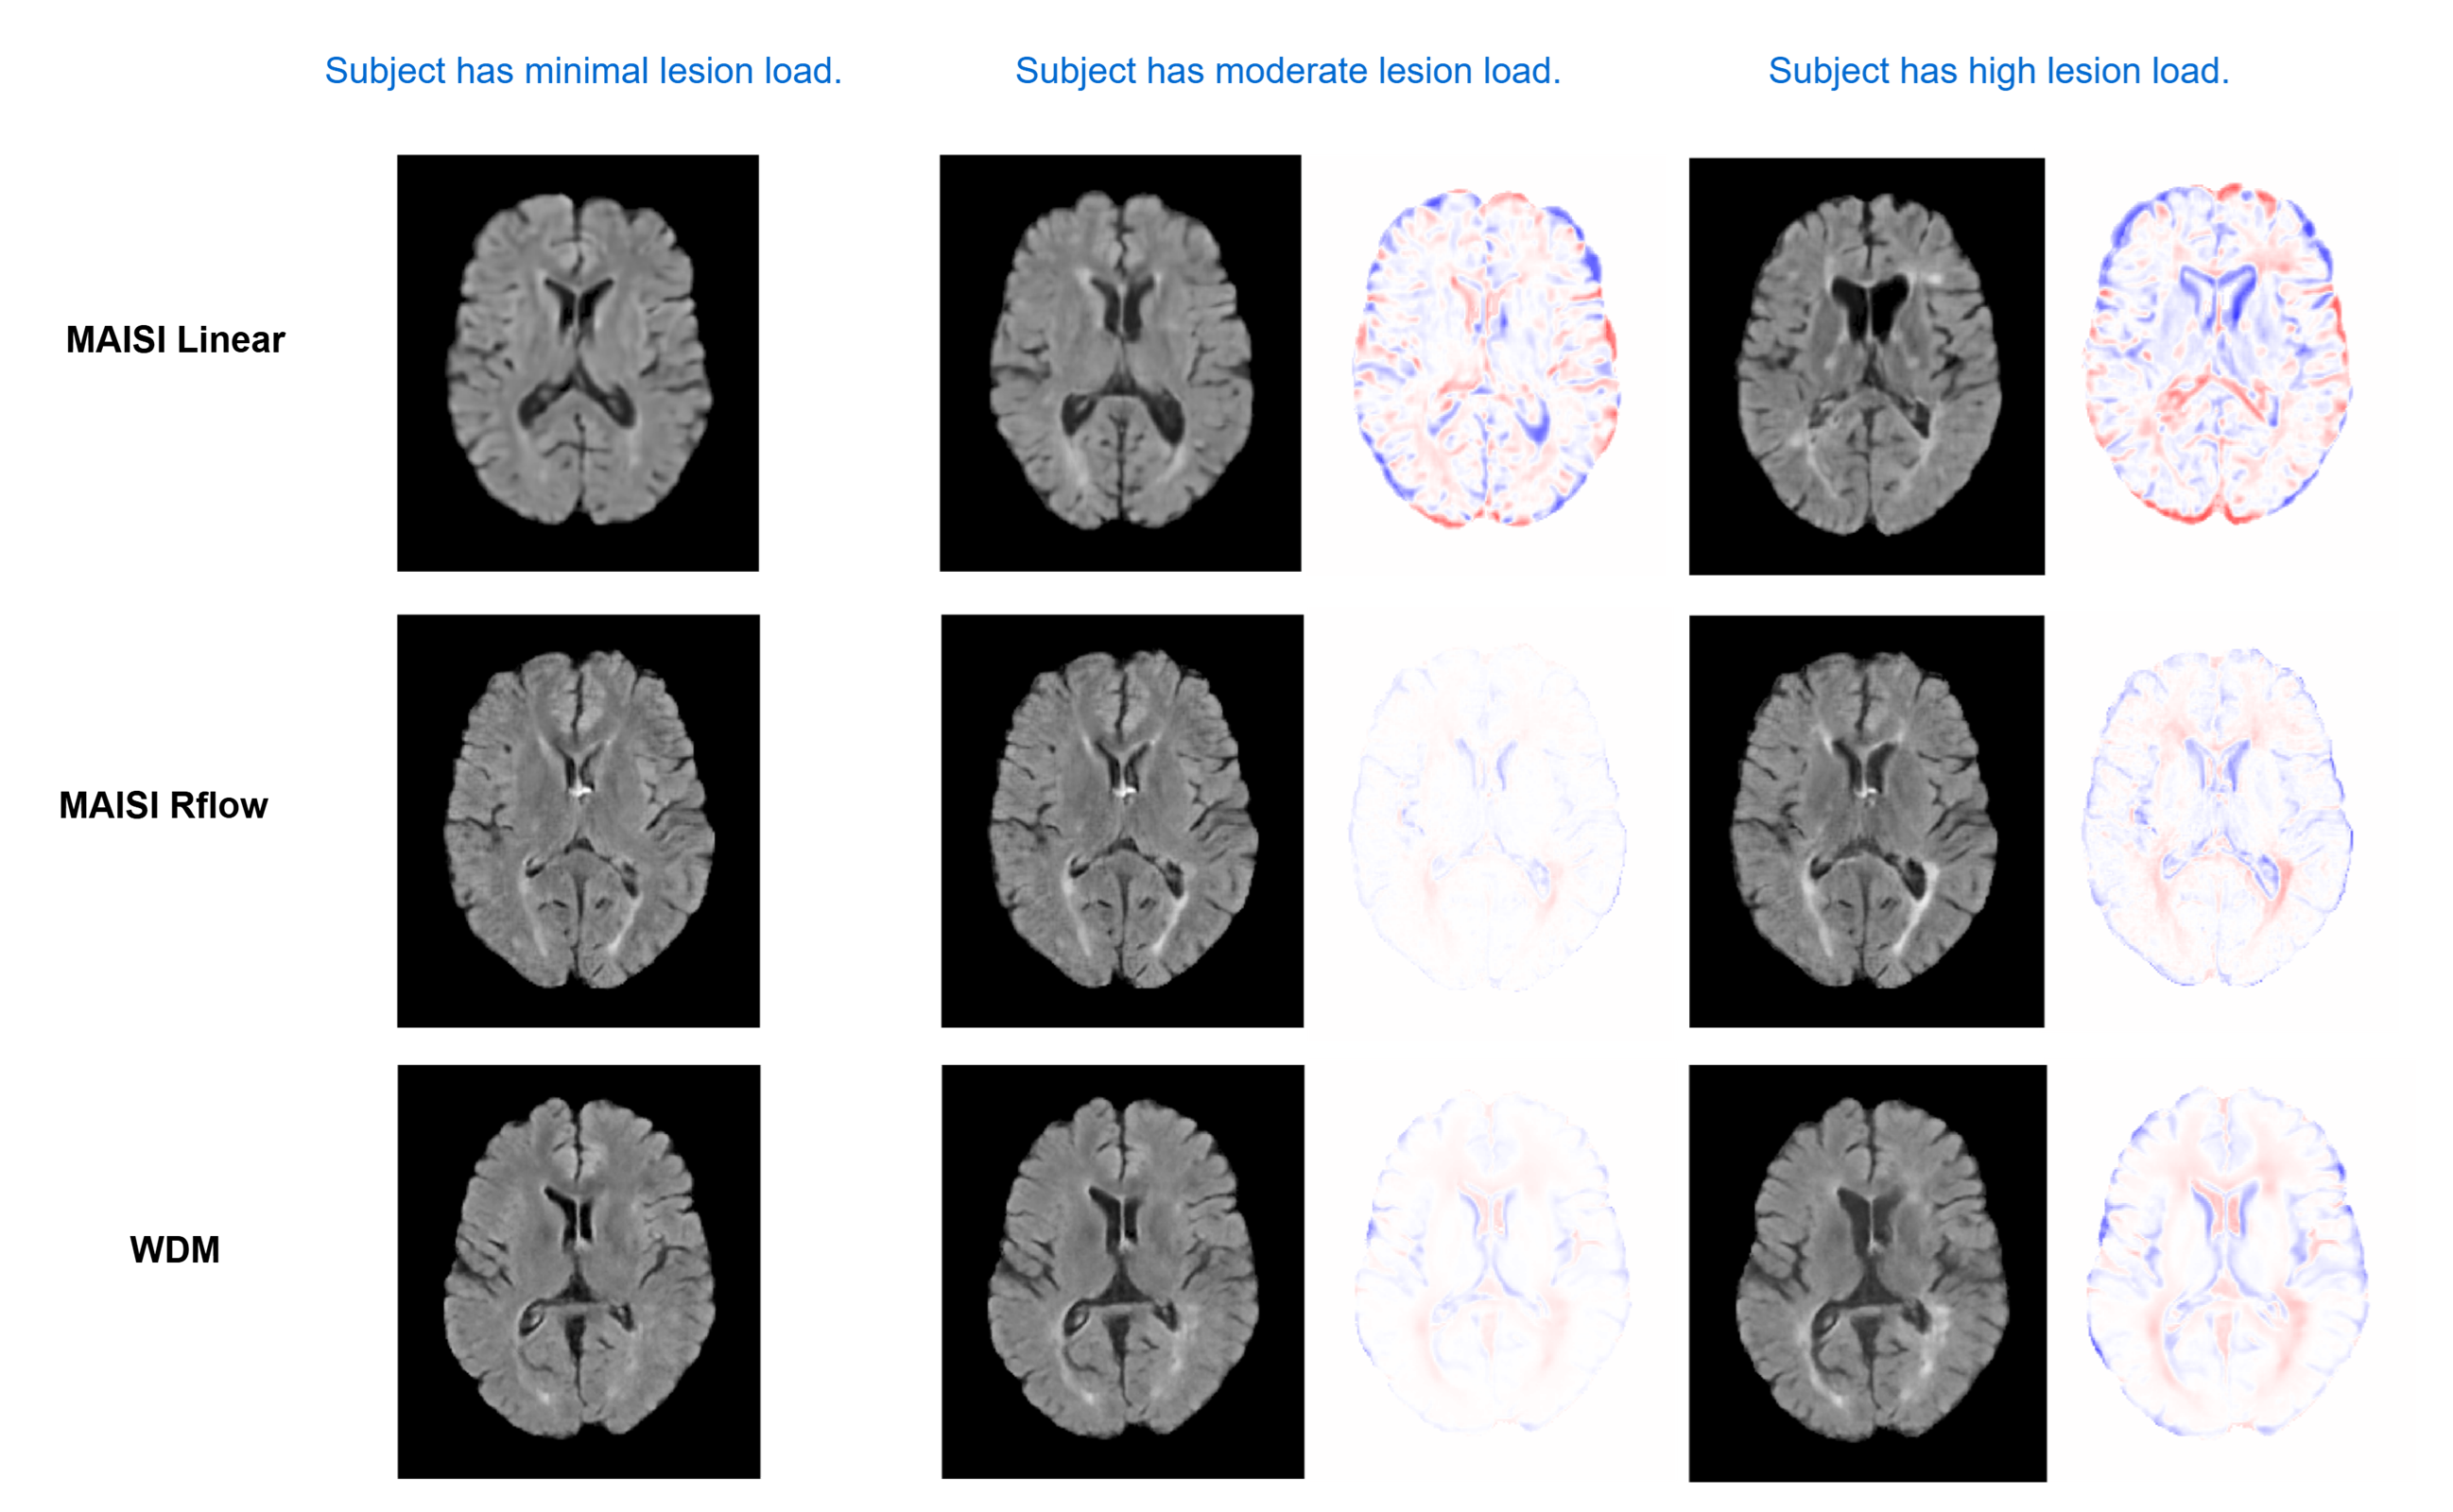

Figure 2: Qualitative comparison of generated counterfactuals for synthesized subjects on the MS dataset for different lesion loads.

For each model–dataset pair we synthesize 1,000 volumes—333 per prompt—then generate medium- and high-level counterfactuals from every low-level baseline (e.g., low vs. moderate/high lesion burden, cognitively normal vs. MCI/AD). Qualitative examples with difference maps appear in Figure 2 and Figure 3.

Qualitative Counterfactual Generation. Figures 2 and 3 show counterfactual MRIs generated by our latent diffusion and adapted WDM models. On the MS dataset, MAISI Linear yields low-quality images with off-target changes, whereas MAISI Rflow and WDM selectively increase lesion load while preserving anatomy. The same holds for ADNI: only Rflow and WDM convincingly depict Alzheimer-related cortical atrophy and ventricular enlargement. These results confirm that the rectified-flow noise schedule boosts image fidelity and counterfactual control in latent diffusion models, and that our approach generalizes to voxel-space diffusion via WDM.